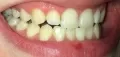

Разошлось мнение двух врачей: одна считает, что кариес на шестнадцатом есть, вторая, что его нет. На рентгене, на шестнадцатом виден темный участок, то есть, скорее кариес есть, чем его нет.

С вашей точки зрения он скорее есть, чем его нет? (речь идет не о поверхностном кариесе, который на рентгене нельзя увидеть, а о более глубоком: среднем или глубоком). Снимок был сделан до лечения.